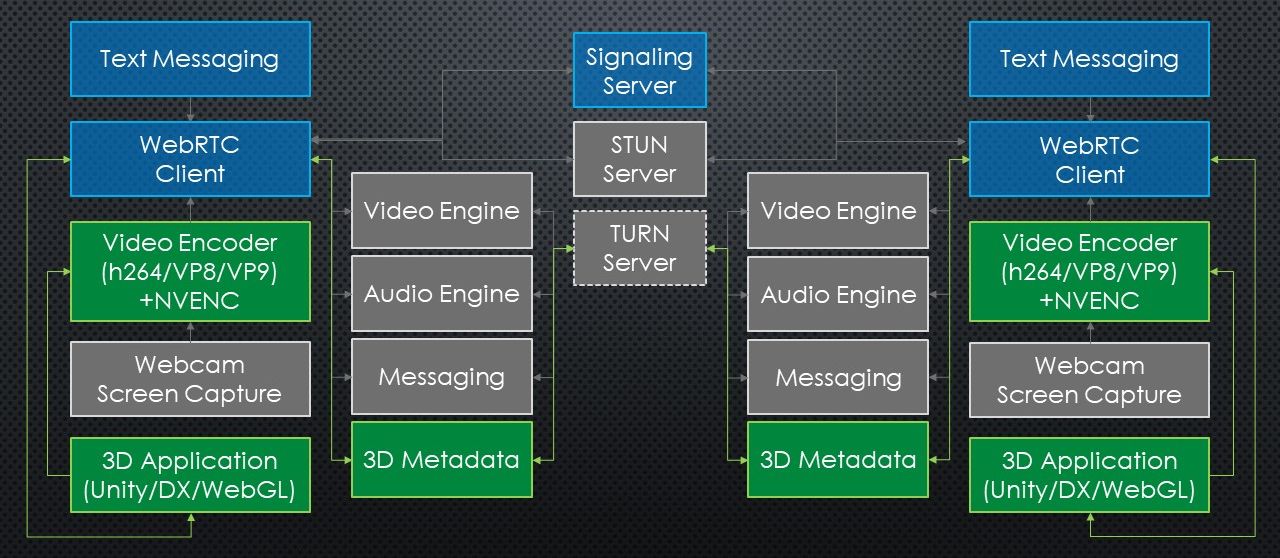

Our solution makes use of the "3D Toolkit" which uses the WebRTC (Web Real-Time Communications) protocols and API as well as the NVEncode hardware encoding library from NVIDIA. The system architecture is depicted in Figure 4.3.

The 3D Streaming Toolkit provides server-side libraries for remotely rendering 3D scenes, client-side libraries for receiving streamed 3D scenes, low-latency audio and video streams using WebRTC, as well as high-performance video encoding and decoding using NVEncode [9].

The WebRTC open source project, released by Google in 2011 for the development of real-time communications between apps, including low latency VOIP audio and video applications. Communication between peers is managed through one or more data channels. The Video Engine is offered as a middleware service to establish a video data channel and to automate buffer, jitter, and latency management. The Audio Engine does the same in regards to audio transmission and is conceived for efficient processing of voice data. Applications can open different data channels for custom messages [9].

The 3DStreamingToolkit’s additions to the typical WebRTC usage are:

-

•

The NVIDIA NVEncode hardware encoder library for real-time encoding of 3D rendered content was added to the video encoders.

-

•

A dedicated data channel manages the camera transforms and the user interaction events. This channel is used to update the HoloLens camera position in the rendering server when the user moves through the room.

These were implemented by means of plugins that engage Unity or native DirectX rendering engines. The Unity server makes use of a native plugin produced by the 3D Toolkit build pipeline. The plugin negotiates with clients to configure a stream, and for encoding and sending visual frame data from Unity to the client.

The core scripts employed by the server are the StreamingUnityServerPlugin, which provides a wrapper around the native plugin that powers the experience. An instance of the wrapper is created by the WebRTCServer, and exposed publicly. The WebRTCServer is the main WebRTC component, which configures the native plugin and handles client input data. Finally, the WebRTCServerDebug enables detailed logging data on request.